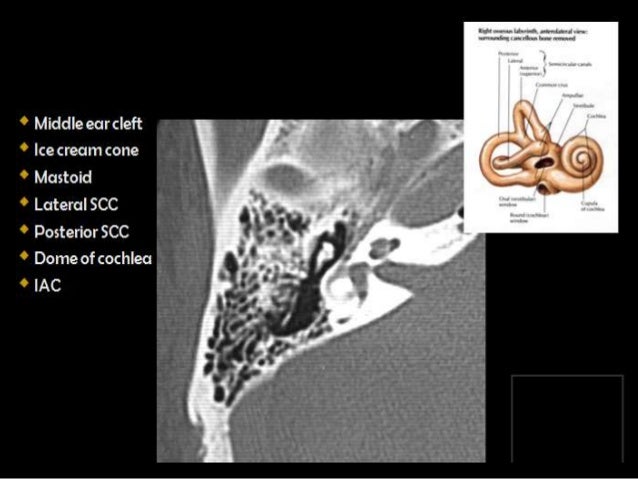

Presentation1.pptx, Ct High Resolution Anatomy Of The Petrous Bone.

Presentation1.pptx, ct high resolution anatomy of the petrous bone. www.slideshare.net

petrous presentation1 modalities

petrous presentation1